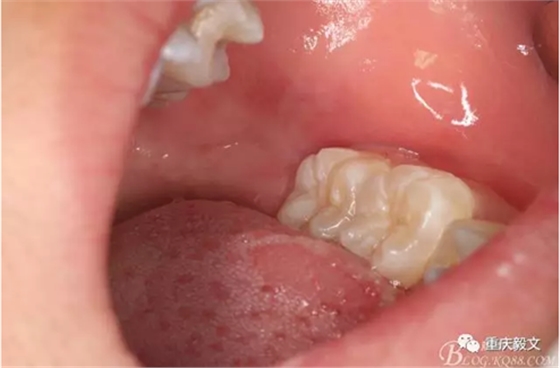

圖2口內(nèi)像,38牙冠未萌出,可探及38牙冠。從此可以結(jié)合x(chóng)光片,判斷38位地位近中埋伏阻生。這樣就確定我們的拔牙手術(shù)方案:切開(kāi)+翻瓣+去骨+分牙的手術(shù)步驟。